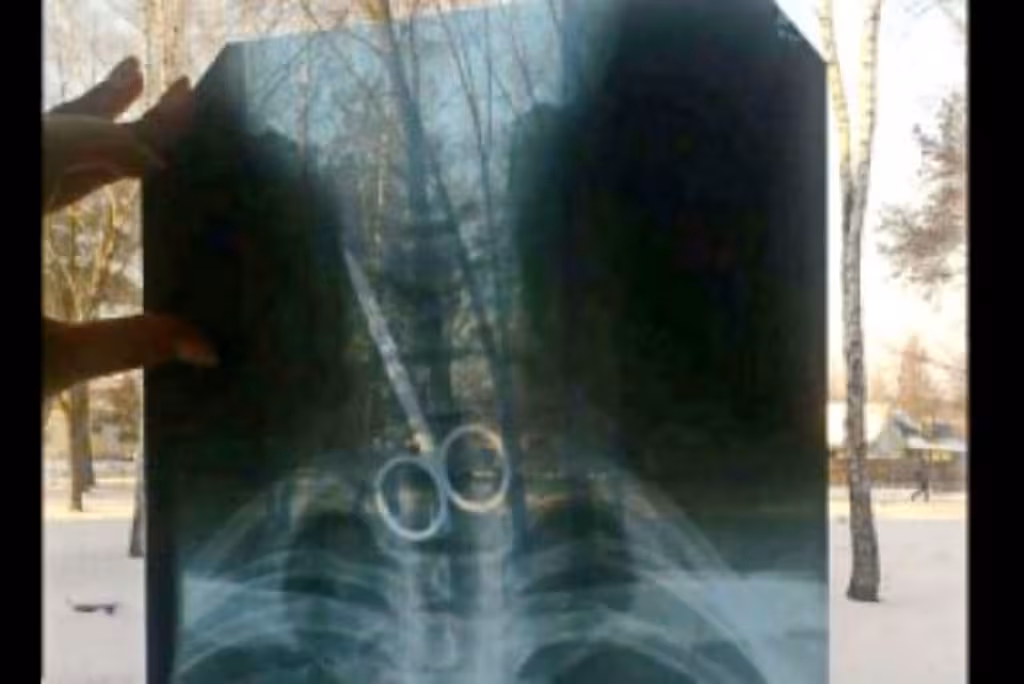

На Самбірщині чоловік проковтнув ножиці: лікарям вдалося його врятувати

Вчора, 18 червня, у Самбірській центральній районній лікарні стався непересічний випадок: чоловік потрапив до медиків проковтнувши ножиці. Лікарі вдало провели складну операцію та врятували його. Про це повідомляє «Голос Самбірщини», з посиланням на інформацією Самбірської міської ради.

«Чоловік проковтнув ножиці, та наші лікарі вміло вилучили їх з організму постраждалого», — йдеться у повідомленні головного лікаря на нараді у міського голови.

Головний лікар Богдан Марчук відзначив, що чоловік страждає на психічні розлади.